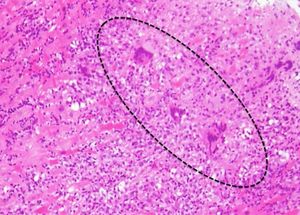

'''호산구성 심근염'''은 심근에 침윤한 호산구의 과립 중에 포함된 eosinophil cationic protein|ECP|호산구 양이온 단백질영어 및 주요 염기성 단백질(MBP) 등의 세포 독성 물질에 의해 발생한다. 방사상의 호산구 침윤 및 탈과립, 심근 세포의 파괴, 그리고 침윤성 염증 세포에 근접한 심근 세포의 손상을 보인다.

'''거대 세포성 심근염'''은 다수의 다핵 거대 세포가 나타나고, 광범위한 심근 괴사가 인정되는 치명적인 심근염이다.

골드 스탠다드는 일반적으로 혈관 조영술 환경에서 수행되는 심근의 생검이다. 심내막과 심근의 작은 조직 표본을 채취하여 검사한다. 심근염의 원인은 생검으로만 확인할 수 있다. 심내막 심근 생검 표본은 조직 병리학(현미경으로 조직이 어떻게 보이는지)에 대해 평가된다. 심근 간질은 부종과 림프구 및 대식세포가 풍부한 염증 침윤을 나타낼 수 있다. 근세포의 국소적인 파괴는 심근 펌프 부전을 설명한다.[12] 또한 면역조직화학으로 표본을 평가하여 반응에 어떤 유형의 면역 세포가 관여하고 어떻게 분포되는지 확인할 수 있다. 또한 특정 바이러스를 식별하기 위해 PCR 및/또는 RT-PCR을 수행할 수 있다.